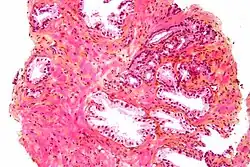

A próstata consiste em tecido glandular e conjuntivo. Células altas em forma de coluna formam o revestimento (o epitélio) das glândulas.[1] Estas formam uma camada ou podem ser pseudoestratificadas.[3] O epitélio é altamente variável e áreas de células cuboidais baixas ou planas também podem estar presentes, com epitélio transicional nas regiões externas dos ductos mais longos.[9] As glândulas são formadas como muitos folículos, que drenam para os canais e, subsequentemente, para 12–20 ductos principais. Estes, por sua vez, drenam para a uretra à medida que passa pela próstata.[3] Há também uma pequena quantidade de células planas, que ficam próximas às membranas basais das glândulas e agem como células-tronco.[1]

O tecido conjuntivo da próstata é composto de tecido fibroso e músculo liso. O tecido fibroso separa a glândula em lóbulos.[1] Ele também fica entre as glândulas e é composto por feixes de músculos lisos orientados aleatoriamente que são contínuos com a bexiga.[10] Com o tempo, secreções espessadas chamadas corpora amylacea se acumulam na glândula.[1]

-

Glândulas microscópicas da próstata